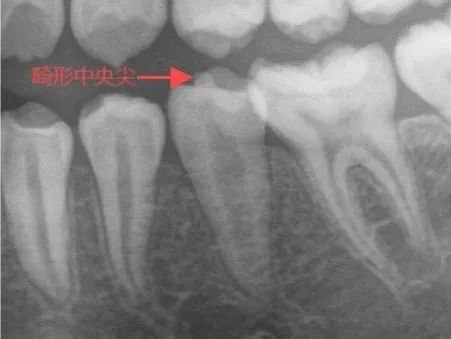

畸形中央尖是牙齿发育过程中的一种异常结构,经常长在下颌的倒数第二颗牙,一般也会在上颌大牙上生长。它一般在大牙的牙窝中间突出的一个圆锥形或圆柱形的牙尖。

2。 X 线检查:通过x线检查,可以帮助我们了解牙根的发育情况、牙髓及根尖周组织的是否处于健康状态。